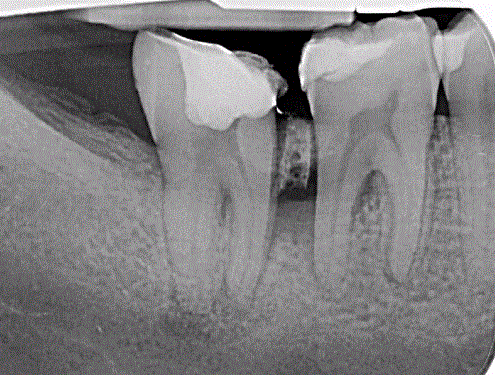

Q

Welche Art der Aufnahme